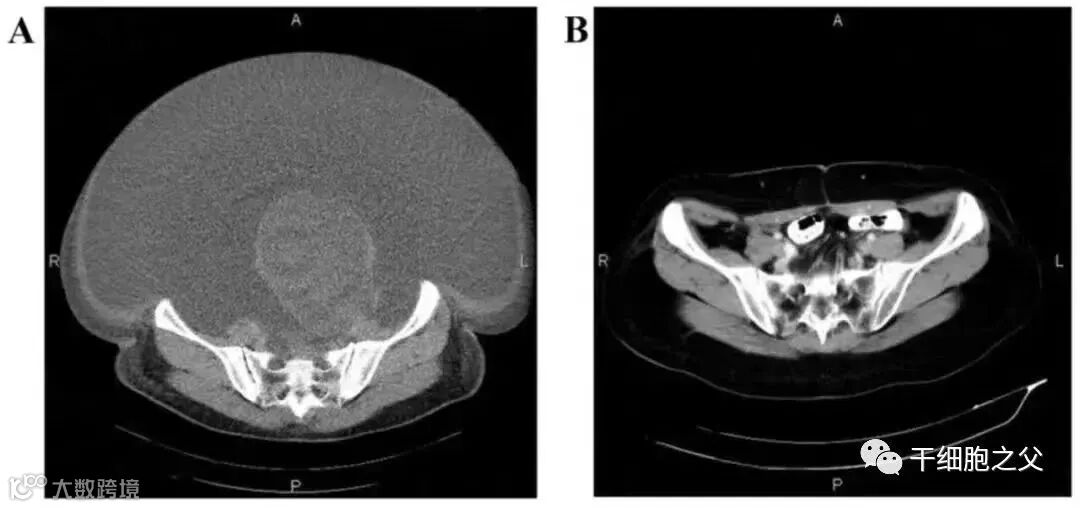

△ NK细胞治疗前和治疗期间的CT扫描结果

案例2:国内一名60岁的卵巢癌晚期患者,在接受了体外扩增,高度活化的同种异体NK细胞的治疗后,CA125水平从11,270降至580,所有腹水都消失了。此外,CT扫描的肿块体积减小,并且没有出现副作用。